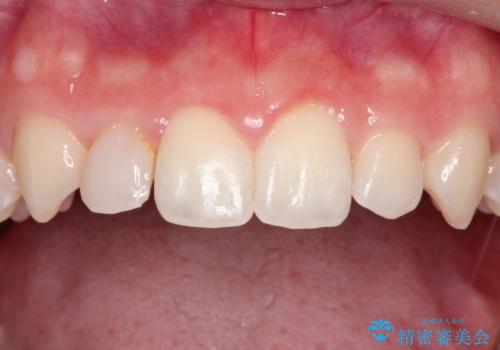

正中の隙間をインビザライン矯正で閉鎖して、右上の2番目の歯にはセラミックを装着する計画としました。

矯正治療とセラミック治療を組み合わせることにより、審美的により良い結果を得ることができました。